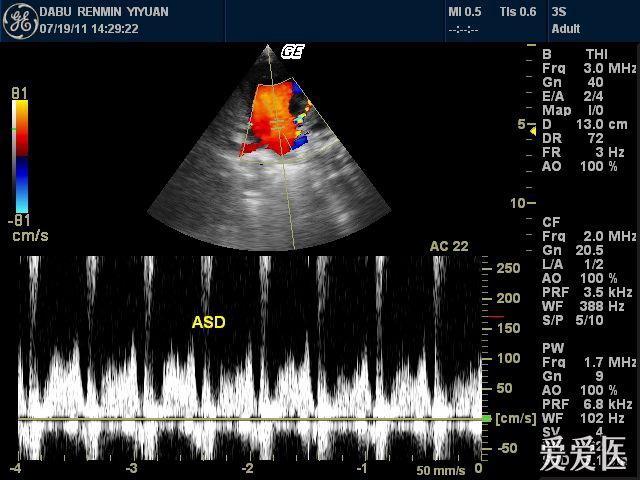

先天性心脏病 :房间隔缺损(ii孔型) - 超声医学讨论版 - 爱爱医医学

图片尺寸768x576